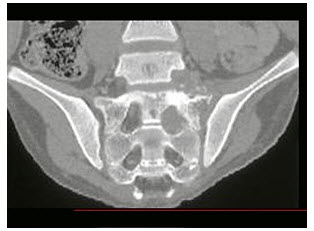

9、多项选择题

男,55岁,尿频,尿痛伴低热乏力1月。如图所示,下列说法正确的是()

A.左侧输尿管多发性狭窄

B.右侧肾积水

C.膀胱变形

D.左侧输尿管结核

E.左侧输尿管癌